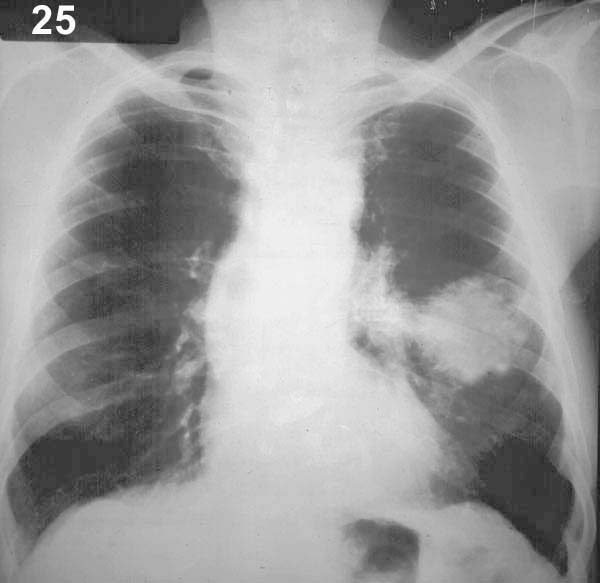

Esquema 25 Comentario placa 25 La sombra irregularmente redondeada del 1/3medio izquierdo tiene un diámetro mayor de 5 - 6 cm, constituyendo una masa. Sus bordes son irregulares y probablemente existe en el hilio izquierdo una imagen nodular de unos 2 cm que podría ser una adenopatía. El conjunto es sugerente de neoplasia y obliga a completar el estudio con los exámenes que permitan comprobar o descartar esta hipótesis. Examine y describa la placa 26 |